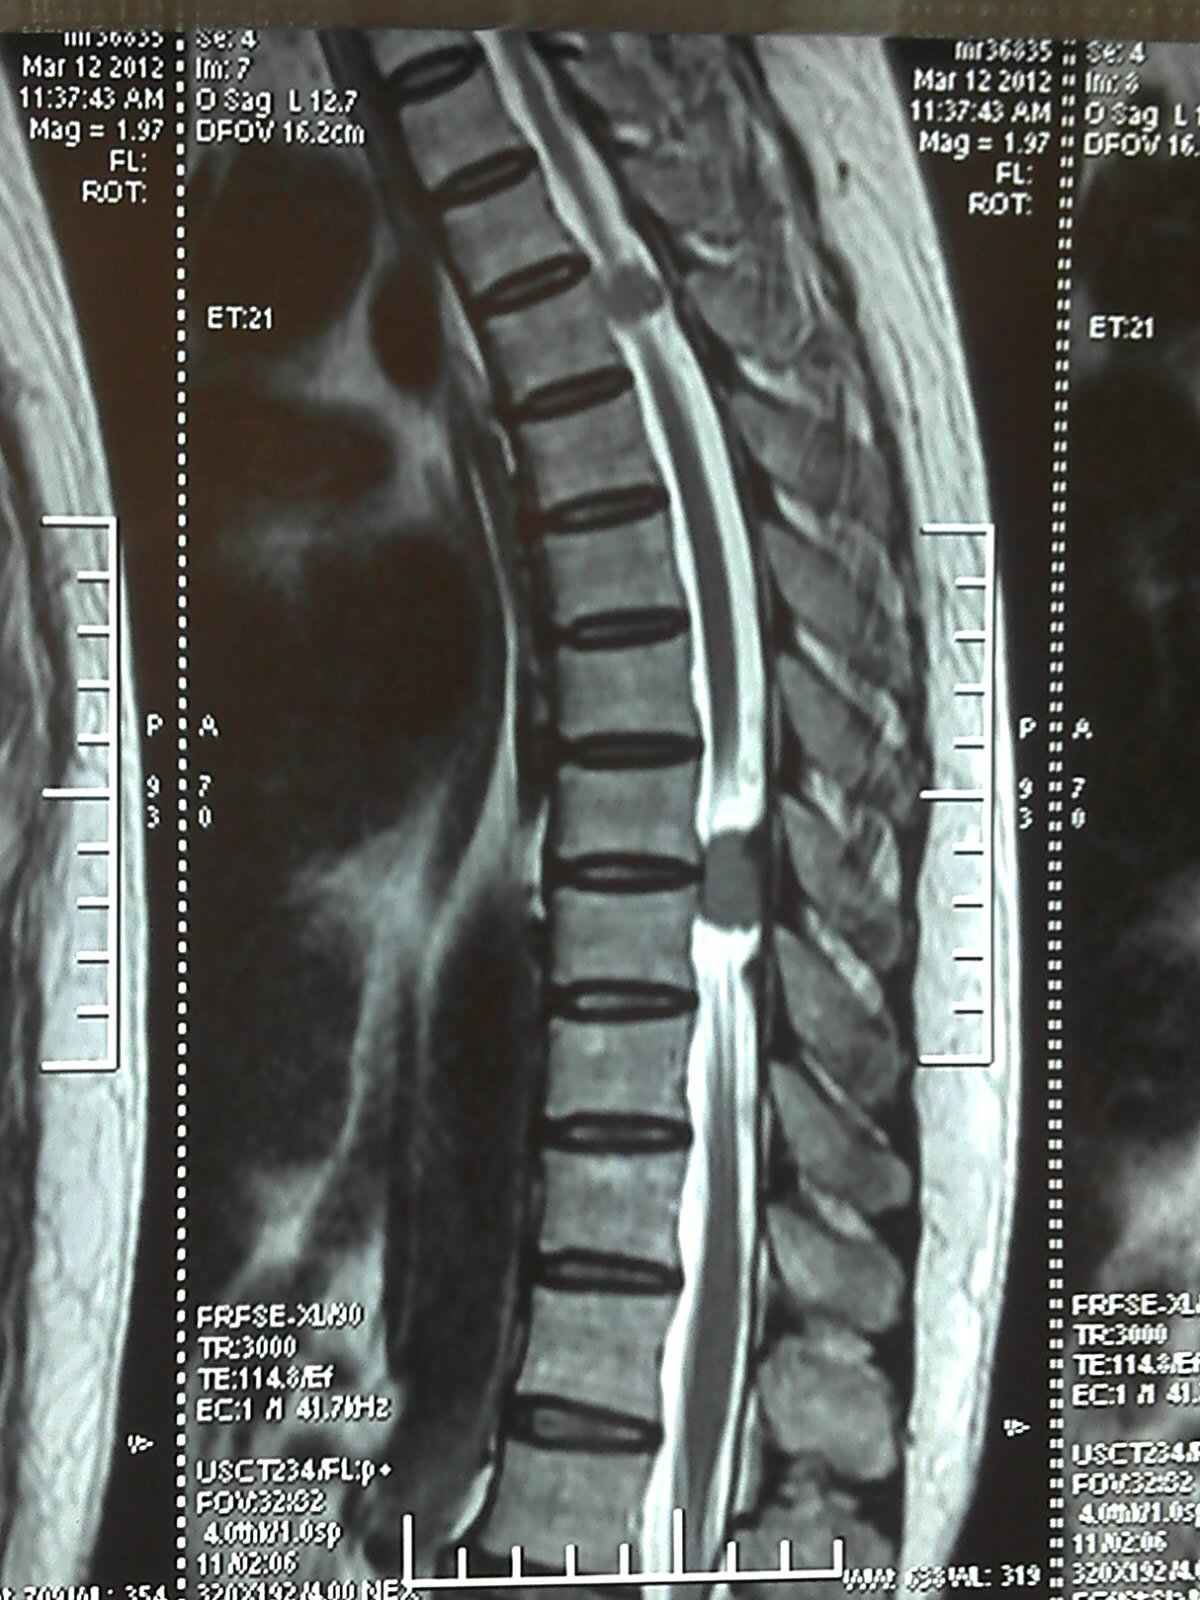

放疗疗效非常好,病人及家属非常满意,但好景不长,幸福的时光往往那是短暂的。好像没过多长时间,病人出现了双下肢无力的症状,检查脊椎核磁显示椎管内多发占位性病变,并出现了胳膊及大腿部位的多个皮下结节。

下图是患者的影像表现: